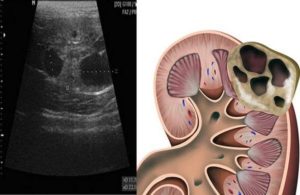

- УЗИ почек, при котором определяется размер, эхогенность и структура (неоднородность тканей почки). Более того, с помощью ультразвука можно определить наличие камней или новообразований, а также признаки воспаления.

Толщина слоя паренхимы – еще один очень важный параметр, в норме составляет 18-25 мм. Этот показатель зависит от возраста пациента: у пожилых людей он может уменьшаться до 11 мм в результате склеротических изменений.

Паренхима является функциональной частью почки, в ней расположены структурно-функциональные единицы – нефроны.

Увеличение показателя может быть признаком отека или воспаления почки, уменьшение свидетельствует о дистрофии органа.

В норме должна четко выявляться граница почечных пирамидок в паренхиматозном слое: эхогенность пирамидок ниже, чем паренхимы. При гидронефрозе дифференциация между ними отсутствует.

Эхогенность паренхимы

Этот показатель определяет состояние почечной паренхимы, ее структуру. В норме она однородна.

Эхогенность – это степень интенсивности отражения звуковой волны от тканей: чем плотнее ткань, тем интенсивнее отражение и светлее изображение на мониторе. Ткани с низкой плотностью имеют слабую эхогенность и визуализируются темными участками. Жидкости и воздух анэхогенны.

К примеру, полостную кисту, содержащую жидкость, специалист описывает как анэхогенное образование. Гиперэхогенность характерна для склеротических процессов в почке (гломерулонефрит, диабетическая нефропатия, опухоли, амилоидоз).